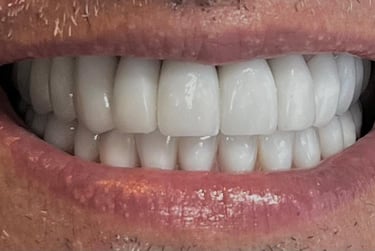

Aspecto Clínico Final - Fotografias originais — nenhuma contém retoques — A cor dos dentes é escolhida de acordo com o gosto e a preferência estética de cada paciente.

Depois

Depois - Restauração em resina associada ao clareamento dental.